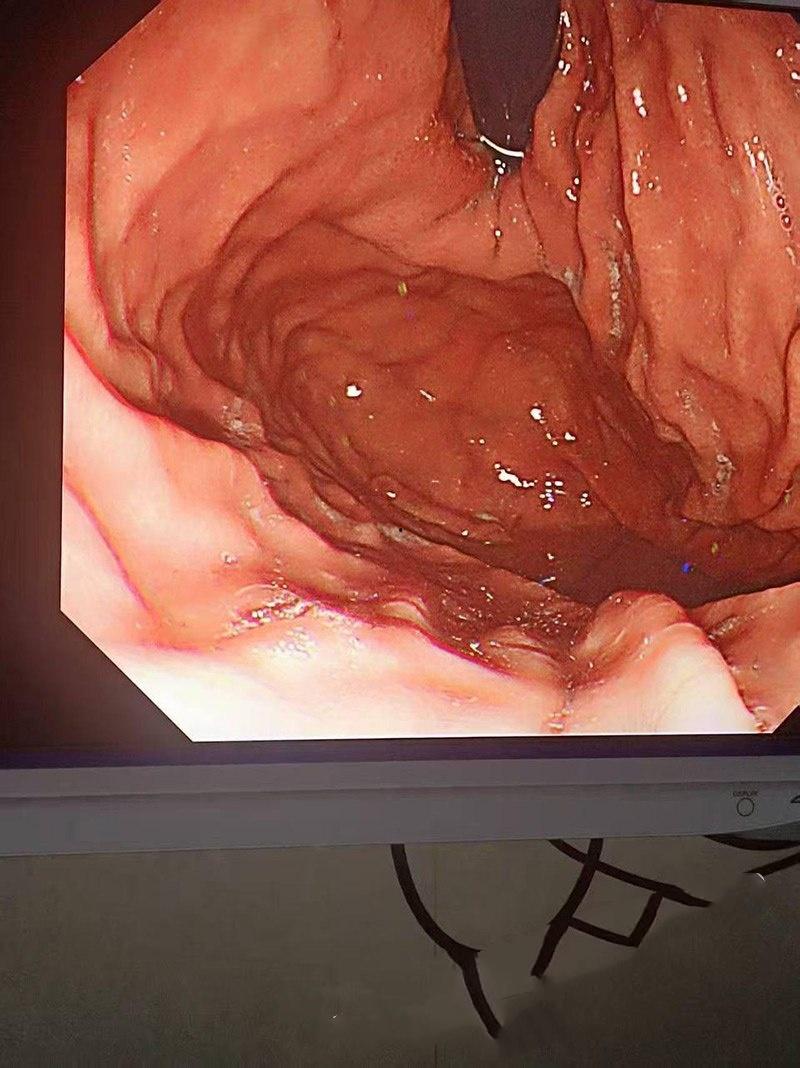

北京同性恋酒吧出大瓜啦!男模被有钱大佬4万包夜带去酒店,有钱人就是变态,现在不玩女人,改玩男人了,沙包那么大的拳头,直接塞进男模屁眼里,男模痛并快乐的享受着,两人玩的那叫一个激情澎湃。

当大佬从男模屁眼将手抽出来时,金戒指竟然卡落在男模屁眼里拿不出来了,没办法,只好深夜送医,在医生专业操作下拿出那枚戒指,不得不说现在的有钱人玩的真花,大家还记得高尔夫球事件吗?这次事件更是有过之而不及。